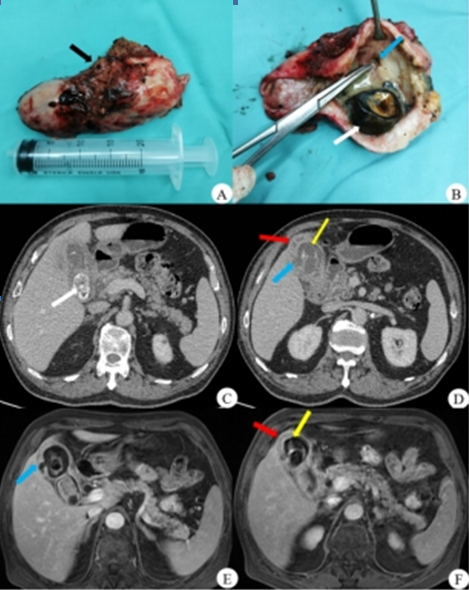

呼和浩特市第一医院医学影像科黄色肉芽肿性胆囊炎病例解析

图片尺寸469x590